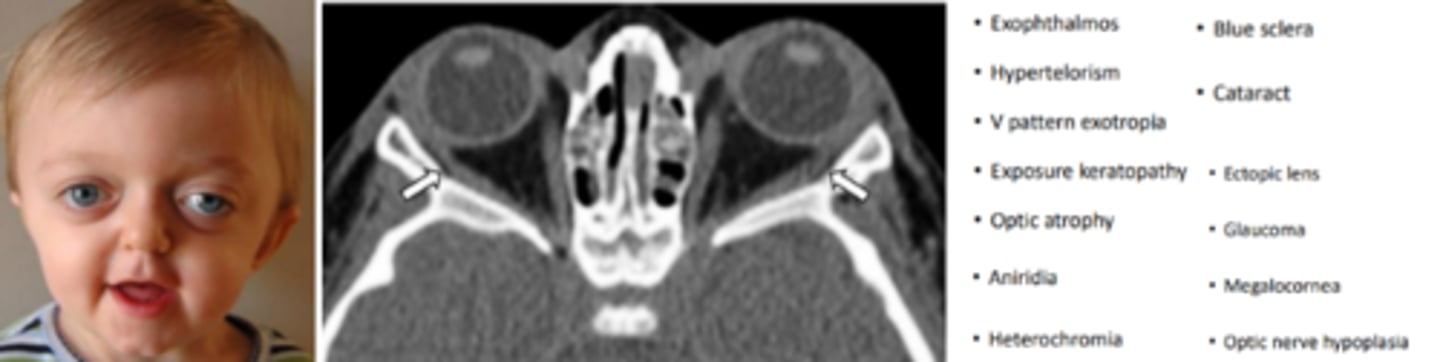

Couzon's disease

the most common cranio-facial syndrome occurring due to mutation of the fibroblast growth factor gene (FGFR2) or by spontaneous mutation 50% of the time. Begins in the first year and completes by the 2nd to 3rd year. Involves brachycephaly, underdevelopment of the maxillary and zygomatic bones, wide cranium, hearing loss, and V shaped palate. Characteristic "frog like face".